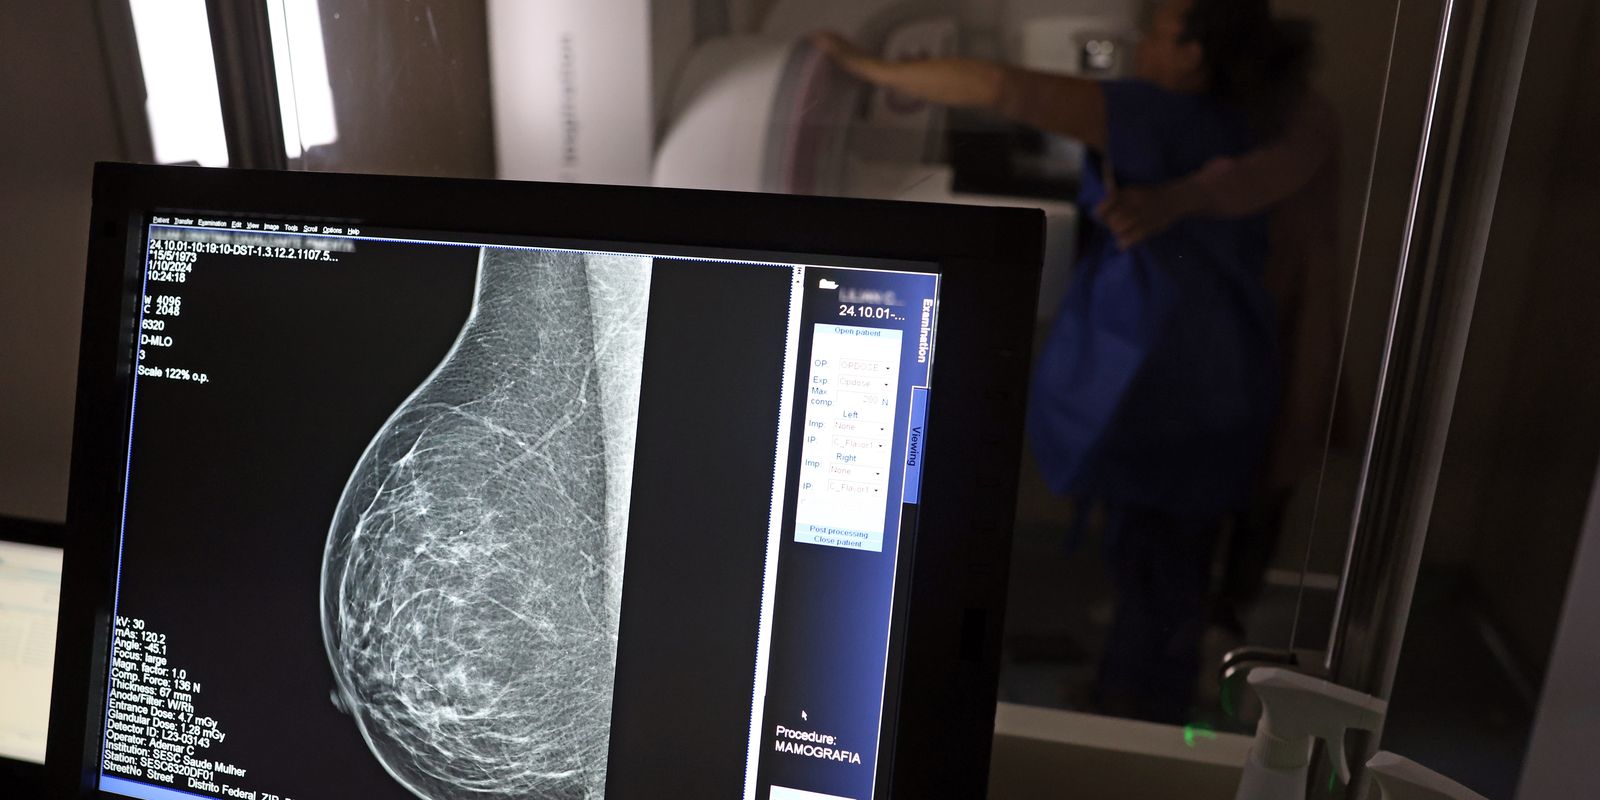

- Falta de acesso a mamógrafos limita prevenção do câncer de mama.